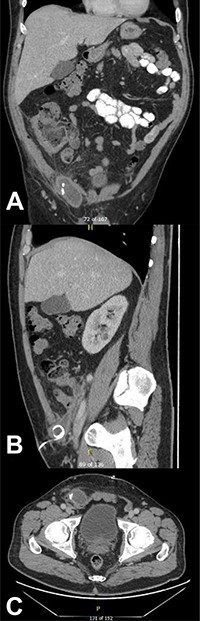

CT of the abdomen and pelvis demonstrating a reduction in size of the fluid collection/abscess in the inguinal hernia sac in (A) coronal (B) sagittal and (C) apical planes.

This collection was drained under ultrasound guidance, and a pigtail catheter was left in situ for 1 week. The patient progressively recovered. A repeat CT of the abdomen and pelvis after a week demonstrated a reduction of the collection (Fig. 3).